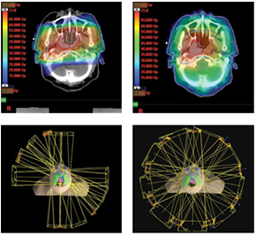

image

Medulloblastoma – affects children. Malignant brain tumour is surgically removed and afterwards, to prevent spread, you want to sterilize the spine with radiation.

A few developments